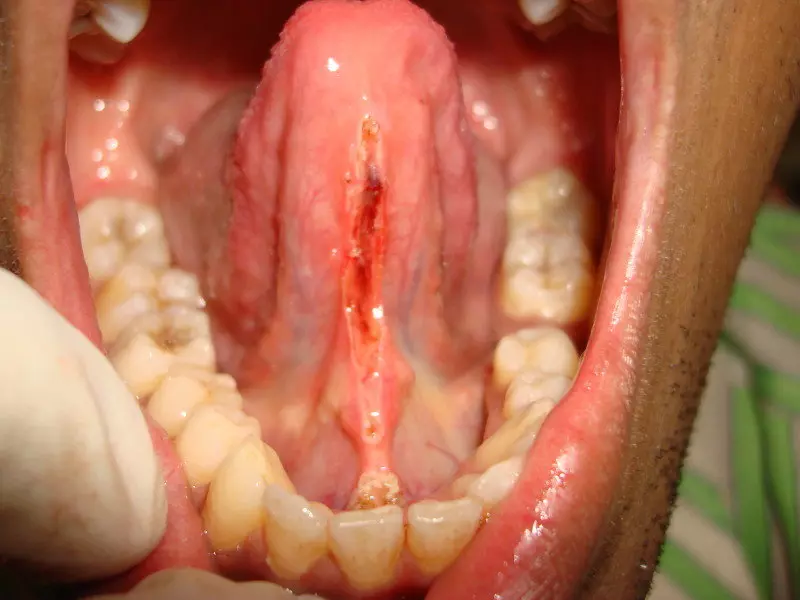

Tongue Tie Surgery

With Lasers

Tongue Tie also known as Ankyloglossia is a high muscle attachment of tongue & floor of the mouth with the back [lingual] surface of gingiva of lower front teeth mainly incisors.

Due to this high attachments patient has difficulties in speaking, eating, breast feeding in children as tongue can’t come out. It also can not touch the upper palate and all tongue movements are restricted.

Laser Dentist Dr Viral Patel Uses state of art laser to remove the high lingual frenum attachment without any bleeding & pain in few minutes only.